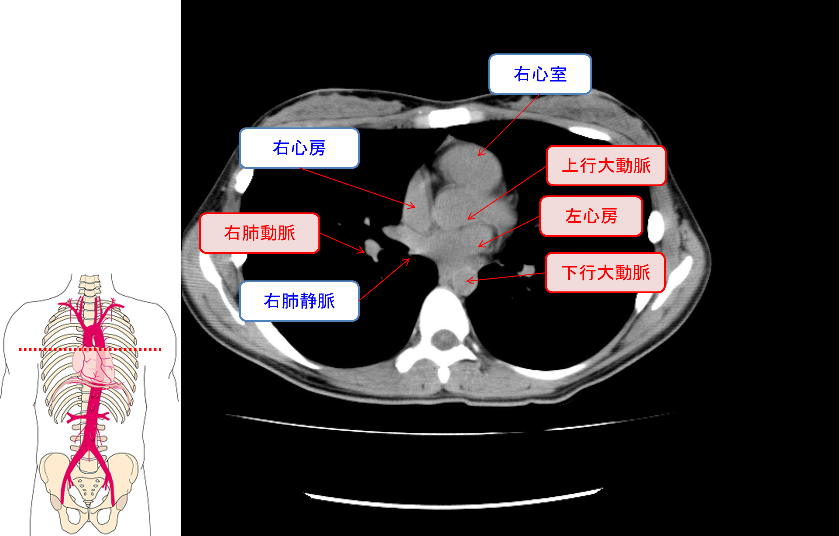

●このセミナーでは、主に胸部単純X線写真とCT、腹部単純写真とCT、脳CTの正常画像と異常画像について話をしています。我々看護師は、診断を仕事としているわけではありませんので必ずしも画像は読める必要はないかもしれません。しかし、臨床所見で異常を疑った場合に「写真を撮影する」と言うことは日常臨床であり、「今写真を撮ったほうがいいのではないか?」と言うタイミングがわかると、適切なタイミングで医師へ報告することができるようになります。そのスキルを磨くためには、普段から臨床所見と画像所見、あるいは検査所見を見比べていく必要があります。診断を目的としない看護師のための画像所見の基礎、ぜひお越しください。

●胸部の解剖、胸部単純写真と単純CT読影の基礎